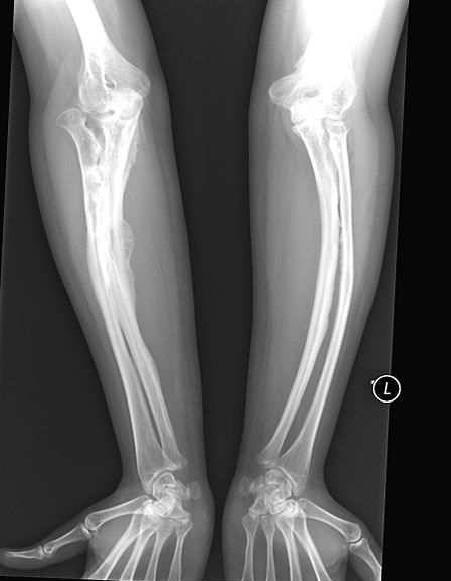

Ženi s povečano krhkostjo kosti je uspelo srečno iti ven poročiti se. Anastasia Marukova, ki so ji postavili diagnozo kot otrok “nepopolna osteogeneza”, preživela veliko težav. Ona je zlomil kosti 40-krat. Oče ni mogel vzdržati življenja s hudo bolnim hčerko in jih zgodaj zapustila pri materi. Toda takrat je Anastasia imela srečo mož – ljubljena oseba jo pospremi povsod, ker neprevidno gibanje ji obljublja novo prelomnico.